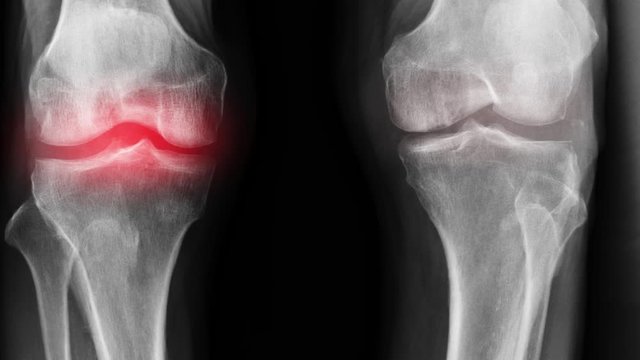

La préparation a été créée à partir de la formule de Sarah Sibanda. Il favorise le processus de guérison du tissu cartilagineux au niveau cellulaire, arrête le processus de détérioration articulaires et élimine la source de l'infection. Le médicament élimine les anomalies dans le liquide synovial et restaure la fonction des articulations, il augmente également la flexibilité des articulations en raison de sa propriété anti-mortification améliorée. On a nommé le produit - Marukaya Cream.

Voici les résultats des personnes qui ont participé aux tests de Marukaya Cream :

Traitement de l'articulation de la hanche d'un patient âgé de 44 ans. La douleur atroce qui a torturé le patient pendant 2 ans, a été complètement guérie :